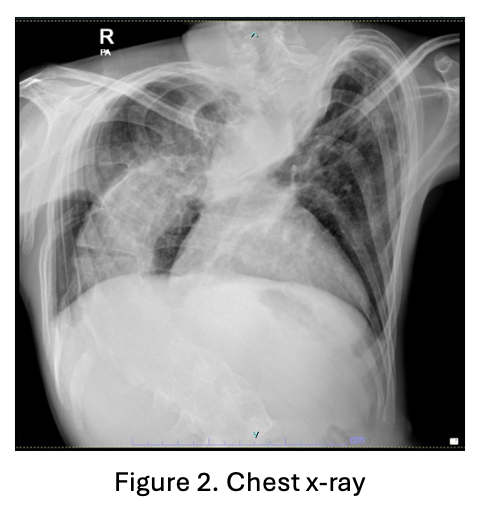

We report a 23-year-old male with pectus carinatum, severe scoliosis, and underweight status (BMI 17.9 kg/m©÷), referred for recurrent pre-hypoxic spells despite optimal medical management of Tetralogy of Fallot (ToF).

The patient came with lethargic, normal blood pressure and heart rate, increased work of breathing and decreased oxygen saturation into 62% on room air. Laboratory test showed increased hemoglobin and hematocrit into 21.7 mg/dL and 71.3% respectively. Bedside transthoracic echocardiography showed subaortic ventricular septal defect diameter 15-16 mm, right to left shunt, severe narrowing infundibulum, right ventricular outflow tract obstruction, with critical pulmonary stenosis.